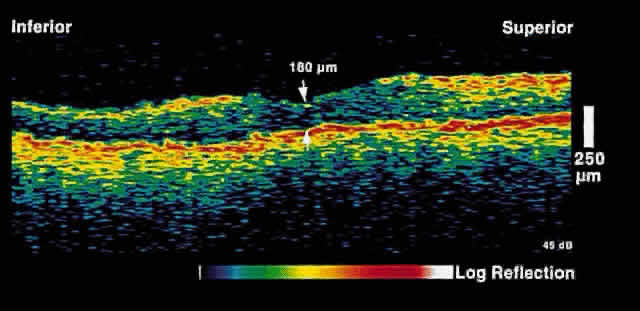

Fig. 3. Several weeks later, an OCT taken through the same area reveals partial

resolution of the neurosensory detachment. Fig. 3. Several weeks later, an OCT taken through the same area reveals partial

resolution of the neurosensory detachment.